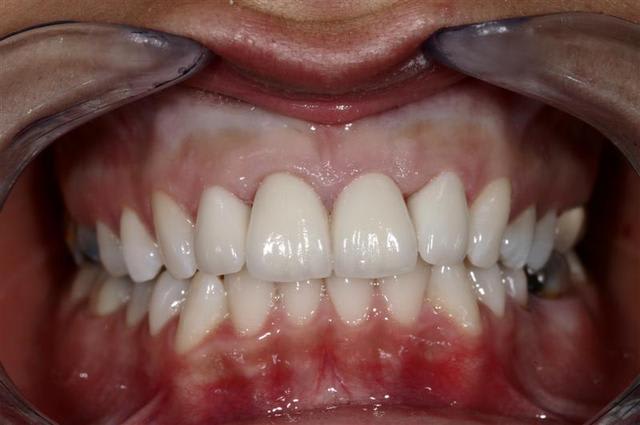

et collées ...

Reste un peu de colle :)

Il y a eu blanchiment

Pour info les compo avaient des vis intra dentinaire.. Encore un qui croyait pas dans le collage..

Sinon pour ton cas, bravo. Espérons que la papille de 21-22 vienne fermer le triangle noir disgracieux assez rapidement.

Controle à 1 semaine, patiente ravi et tout sourire... moi aussi :)